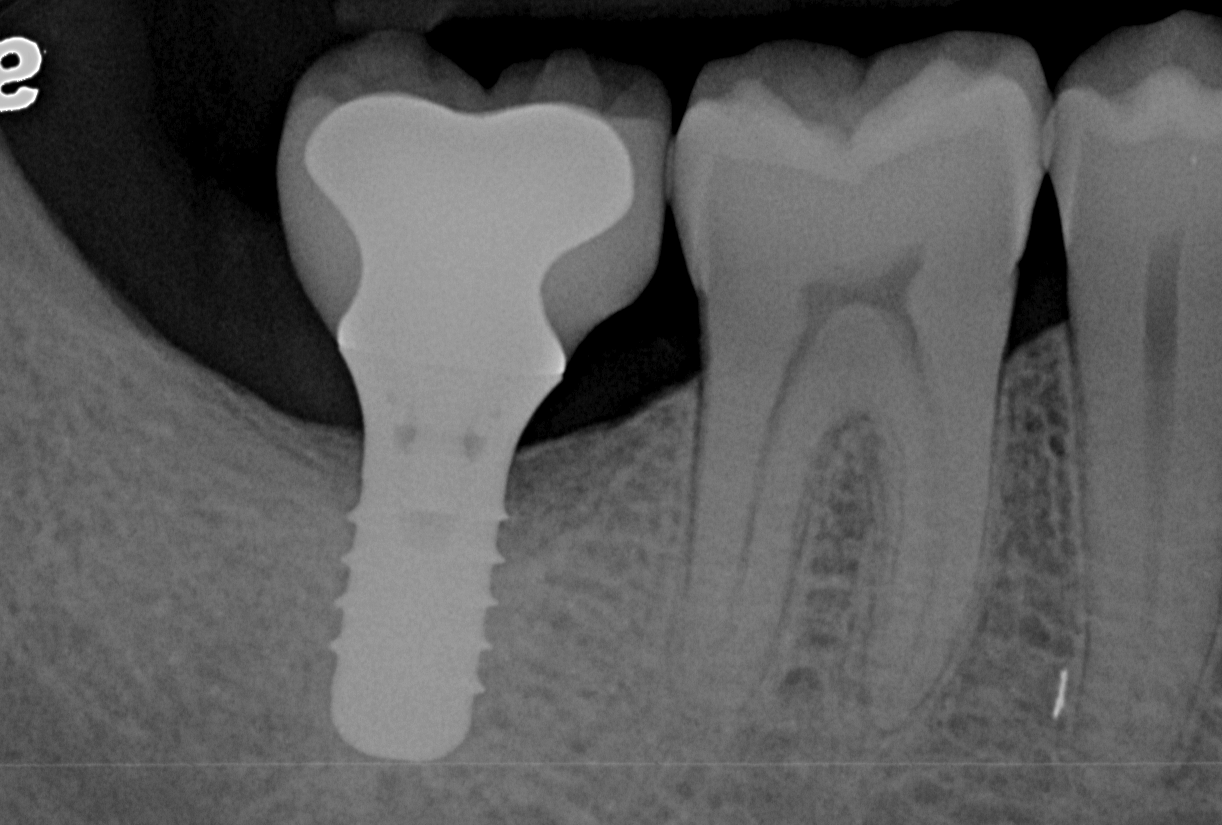

At 1 year following treatment, probing depths are now 3 mm with an absence of bleeding.

Figure 6

Figure 7